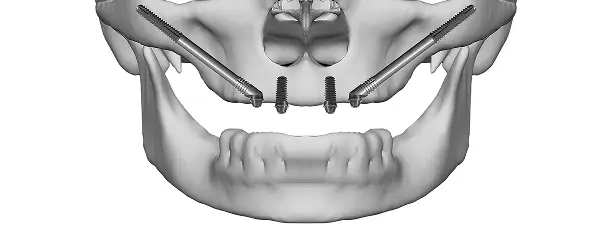

Implanturi zigomatice

Alegem acest tratament atunci când osul maxilar este foarte redus. Implanturile zigomatice sunt ancorate în osul zigomatic și oferă sprijin pentru proteze imediate, fără să fie necesară adiția osoasă.